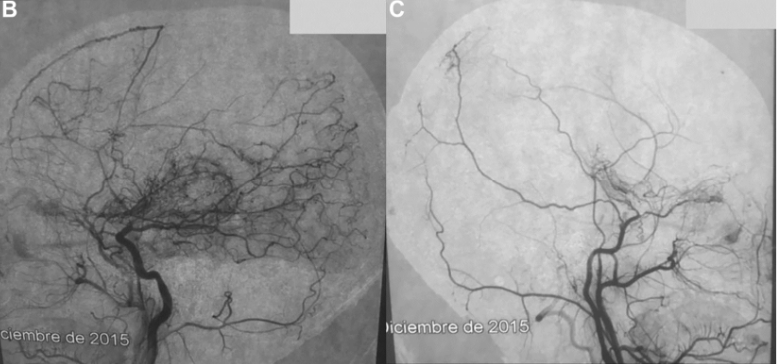

术前DSA显示双侧颈内动脉、右侧眼动脉远端和后交通动脉远端完全闭塞,双侧基底节烟雾络脉(B,左颈内动脉和颈外动脉分支;C,右颈内动脉和颈外动脉分支)。